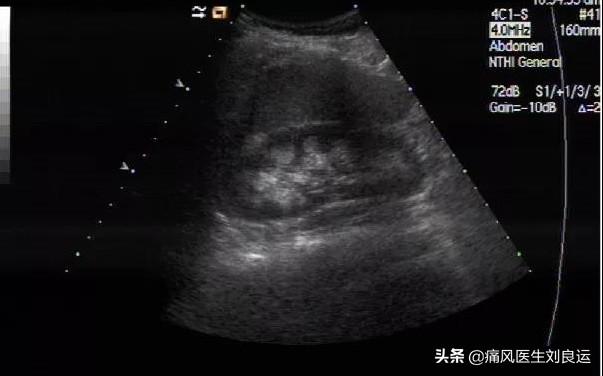

在所有风险因素中,高BMI和肾功能受损对痛风的影响最大。大约有20%左右的痛风病人可以发生肾内尿酸性结石,这是因为尿酸在肾脏实质内沉积而成。

尿酸盐在肾髓质或乳头处沉淀,析出尿酸盐结晶,引起间质炎症,继而纤维化,引起肾小管萎缩,折细动脉硬化而损害肾功能。

• (1)慢性尿酸性肾病:长期高尿酸血症患者容易出现肾小管间质的慢性病变,早期多数患者无临床表现,症状的严重程度与高尿酸血症的持续时间和痛风发作的幅度都有关。过量的尿酸盐在肾脏沉积,可以导致肾间质纤维化和肾动脉硬化。并且出现肾内的痛风石在皮髓交界处及髓质深部沉积。在长期痛风病史的患者中,肾表现为肾内痛风石形成,还有纤维形成、肾小球硬化、动脉硬化及动脉壁增厚。晚期痛风性肾病会出现水肿、高血压、低蛋白血症,并且表现为逐渐加重的肾衰竭,甚至发展为尿毒症。

• (2)急性尿酸性肾病:由短时间大量尿酸结晶堆积在肾集合管、肾盂和输尿管所致。由于尿液中尿酸浓度骤然增高而形成过饱和状态,显微镜下可以见到管腔内尿酸结晶沉积,形成晶体或呈雪泥样沉积物。可以阻塞肾小管,近端肾小管扩张,但肾小球结构正常。这些沉积物可以导致梗阻及急性肾衰竭。

• (3)痛风性肾结石:一般多发生在青壮年,左右侧发病相似。尿酸性肾结石占泌尿系结石发病率的8~10%,约25%的痛风病人有泌尿系结石。一般表现为疼痛、血尿、尿中排出砂石、感染、梗阻等。当结石引起梗阻时导致肾积水、肾盂肾炎、肾积脓或肾周围炎,感染可加速结石的增长和肾实质的损害。